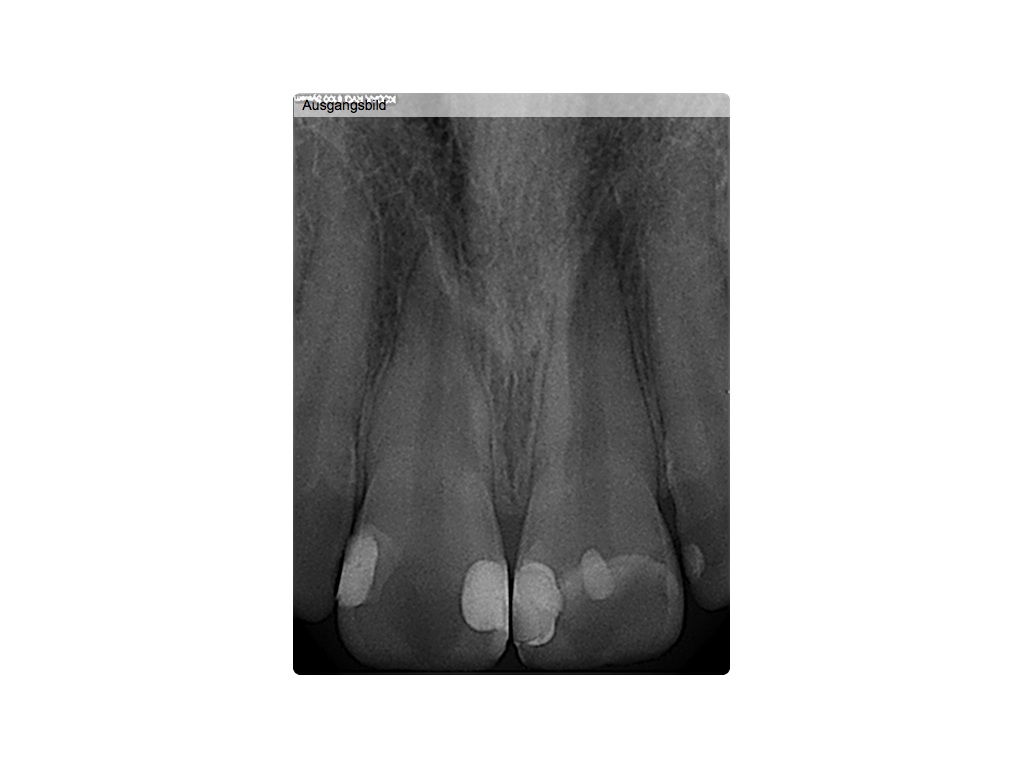

Hätten Sie es gesehen? (2)

Ausgangsbild